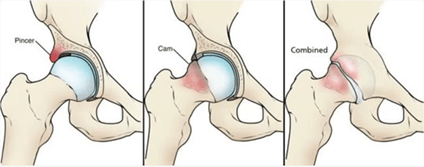

1. Choque o impingement femoroacetabular (FAI)

El choque femoroacetabular o impingement de cadera es una patología en la que existe un contacto anómalo entre el fémur y el acetábulo durante el movimiento. Puede presentarse en tres formas: tipo CAM (prominencia ósea en la cabeza/cuello femoral), tipo PINCER (en el acetábulo) o mixta (combinación de ambas).